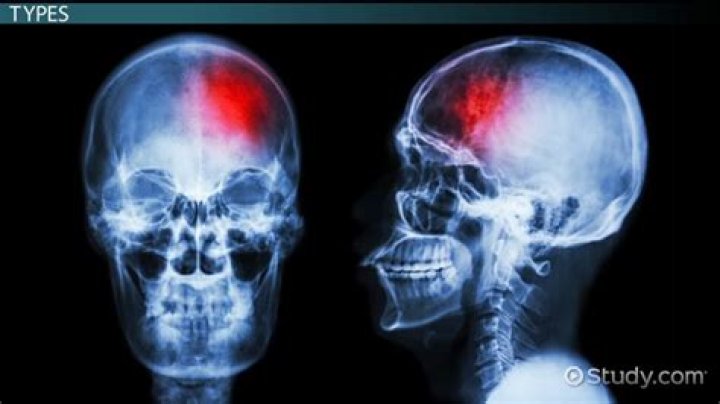

Can hematomas be dangerous?

Dangerous Hematomas Subdural or epidural hematomasepidural hematomas Epidural bleeds from arteries can grow until they reach their peak size 6–8 hours post-injury, spilling 25–75 cubic centimeters of blood into the intracranial space. As the hematoma expands, it strips the dura from the inside of the skull, causing an intense headache. › wiki › Epidural_hematoma

, or hematomas within brain or spinal tissue, can be particularly dangerous. The swelling associated with hematomas in these locations can cause damage to the brain or nerve tissue.